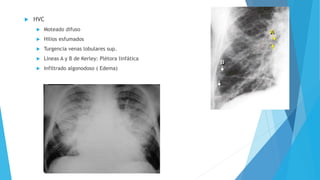

 HVC

 Moteado difuso

 Hilios esfumados

 Turgencia venas lobulares sup.

 Líneas A y B de Kerley: Plétora linfática

 Infiltrado algonodoso ( Edema)